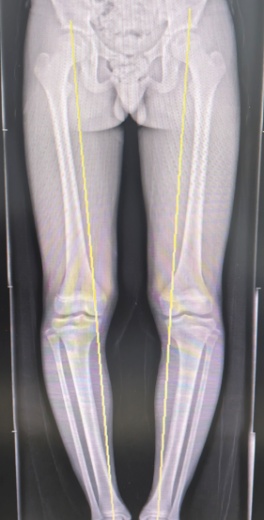

患者站立位力线

科室主任梁捷予接诊后,为小李进行了全面的检查和评估后发现:小李的O型腿导致双下肢受力线严重偏移,走路、跑跳时的重量几乎全部压在膝盖内侧,长期的超负荷压力,不仅磨坏了关节内的半月板,还引发了一系列结构改变和疼痛症状。